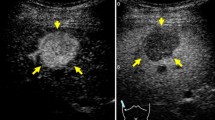

The internal echoes of HCCs smaller than 10 mm are almost hypoechoic (low level) or isoechoic, and the number of such low-level echoes increases with cell density. When tumor growth occurs as multistep hepatocarcinogenesis, fatty change is most frequently observed (36.4%) at a tumor diameter of 10–15 mm [7], and internal echoes of these HCCs are hyperechoic. When the diameter of an HCC reaches 20 mm or more, typical US patterns such as the “mosaic pattern,” “peripheral sonolucency (halo),” “lateral shadow,” and “posterior echo enhancement” can be recognized [8,9,10,11]. Findings of “mosaic pattern,” “posterior echo enhancement,” and “lateral shadow” show a higher accuracy (≥ 70%) and specificity (≥ 90%) in diagnosing HCC than metastatic liver cancer. With an increase in the size of the tumor, the frequency of observation of these US findings increases. However, these typical US findings are less frequently observed in smaller HCCs. The “halo sign” corresponds to the thin fibrous capsule of the HCC [12,13,14,15] (Figs. 1a, b). Correspondence between the sonographic halo sign and a histological capsule has been reported to be 90.1% [16]. The “lateral shadow,” which is a linear US feature observed at the edge of a tumor, represents the refraction that occurs when ultrasound passes through spherical tissue and the surrounding tissue at different speeds (Figs. 1c, d). Posterior echo enhancement arises posterior to any lesion that attenuates sound less than the surrounding tissue; the intensity of the transmitted ultrasound beam is relatively preserved distal to the lesion [3]. However, posterior echo enhancement is not specific to HCC; this finding is also associated with hemangiomas and cystic lesions.

A case of newly developed hepatocellular carcinoma (HCC) (maximum diameter 26 mm) in Segment 7. Computed tomography (CT) shows a low attenuation area in Segment 7 (a). Conventional ultrasound shows a mosaic pattern nodule with posterior wall enhancement (arrowhead) and halo image (thick arrow) (b). A case of hepatitis C virus-related cirrhosis and a newly developed HCC in Segment 4 (c). Conventional ultrasound shows a high echo nodule with a typical lateral shadow (thin arrows) (d)